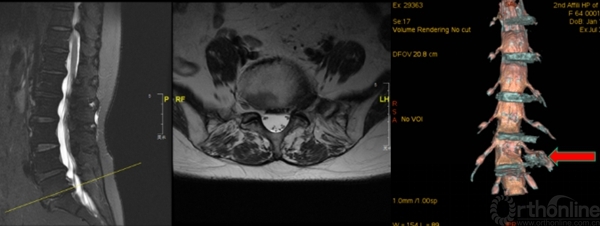

3D-MRI:普通MRI无异常,3D-MRI发现游离髓核,行脊柱内镜取出游离髓核

3D-MRI:对一些特殊类型的椎间盘突出(如极外侧腰椎间盘突出)可起到更加准确的诊断作用

怀疑融合临近节段极外侧突出,选择性神经根阻滞术明确诊断